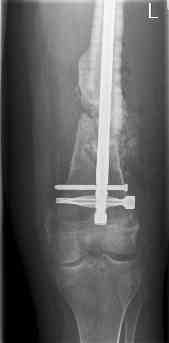

16 yr old boy, high energy motorcycle trauma trauma in July 2005 with:

- hip dislocation + acetabular fracture L

- distal femoral fracture L

- tibial shaft fracture L

- metatarsal fractures L

July 05

july 05: LISS femur, LCP plate tibia, double recon. plate post. acetabulum